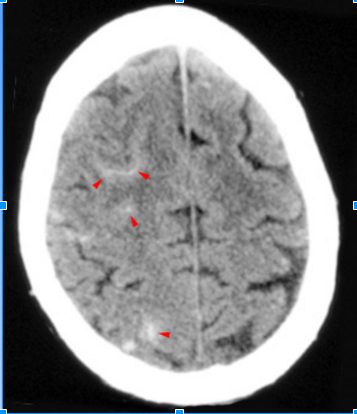

What (arrowheads) fills the sulci over the

right cerebral convexity in this subarachnoid hemorrhage?

See Picture

High density blood